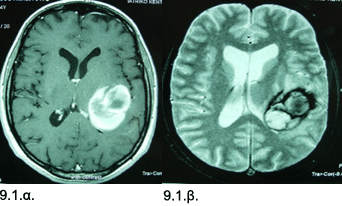

Εικόνες 9.1.α. & 9.1.β. Μαγνητική τομογραφία δείχνει ένα πολύ μεγάλο αιμάτωμα στην κροταφοβρεγματοινιακή συμβολή στο αριστερό εγκεφαλικό ημισφαίριο σε εγκάρσια τομή Τ1 [9.1.α.] και άλλη απεικόνιση Τ2 που δείχνει την περιοχή του αιματώματος και την υποκείμενη βλάβη, δηλ. το σηραγγώδες αιμαγγείωμα του οποίου η ρήξη προκάλεσε την αιμορραγία [9.1.β.].

Ιστορικό: Γυναίκα 35 ετών, με αιφνίδια και ταχέως επιδεινούμενη κεφαλαλγία, μεγάλη αδυναμία χεριού και ποδιού δεξιά, και μεγάλη δυσχέρεια εκφοράς του λόγου (κινητική αφασία). Κατά τον απεικονιστικό έλεγχο διαπιστώθηκε ένα μεγάλο αιμάτωμα, διαμέτρου 4.5 εκ. στην συμβολή κροταφικού, βρεγματικού και ινιακού λοβού αριστερά. Στην εξέταση, διαπιστώθηκε δεξιά κροταφική ημιανοψία. Η ασθενής υποβλήθηκε σε επείγουσα κρανιοτομία αριστερά και αφαίρεση του αιματώματος και του σηραγγώδους αιμαγγειώματος που είχε ραγεί. Η μετεγχειρητική πορεία ήταν ομαλή και η ασθενής δεν ανέπτυξε άλλα νευρολογικά προβλήματα. Μέσα στο πρώτους έξι μήνες, βελτιώθηκε πλήρως η μυϊκή αδυναμία και αποκαταστάθηκε σχεδόν πλήρως η ομιλία.